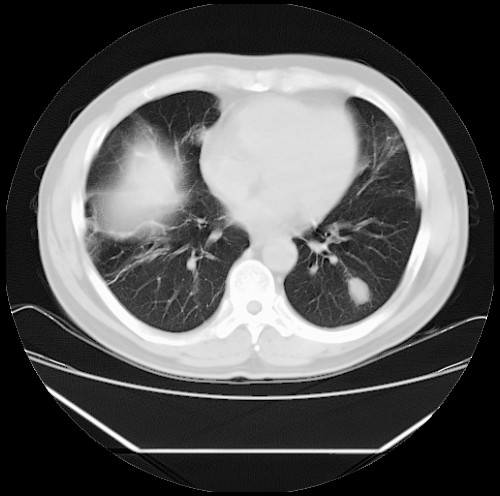

标题: CT22085:双肺多发结节

男,44岁,咳嗽,痰中带血2天。

病灶大部分位于胸膜下,结节大小相差不是很大,肺尖太干净。这种结核没见过,我认为可排除。

首先考虑转移,不除外肉芽肿、真菌感染。建议查其它。

除肺内及胸膜下可见多发大结节外,在肺小叶中心核、小叶间隔及支气管血管束上亦可见多方小结节,可以认为是随机分布。考虑转移可能性大。

仔细观察病灶形态,病灶边界部分清楚,结合临床症状,首先考虑转移,纵隔内多个肿大淋巴结影。

双肺血管纹理末端多发类圆形结节,边界光滑清晰 气管前腔静脉后淋巴结肿大

考虑转移瘤

沿血管分布,位于血管末端。转移瘤多见,血行性菌栓也可见到。

本例双肺多发类圆形高密度灶,边清,结合病史多考虑双肺多发转移改变,可以结合实验室检查。